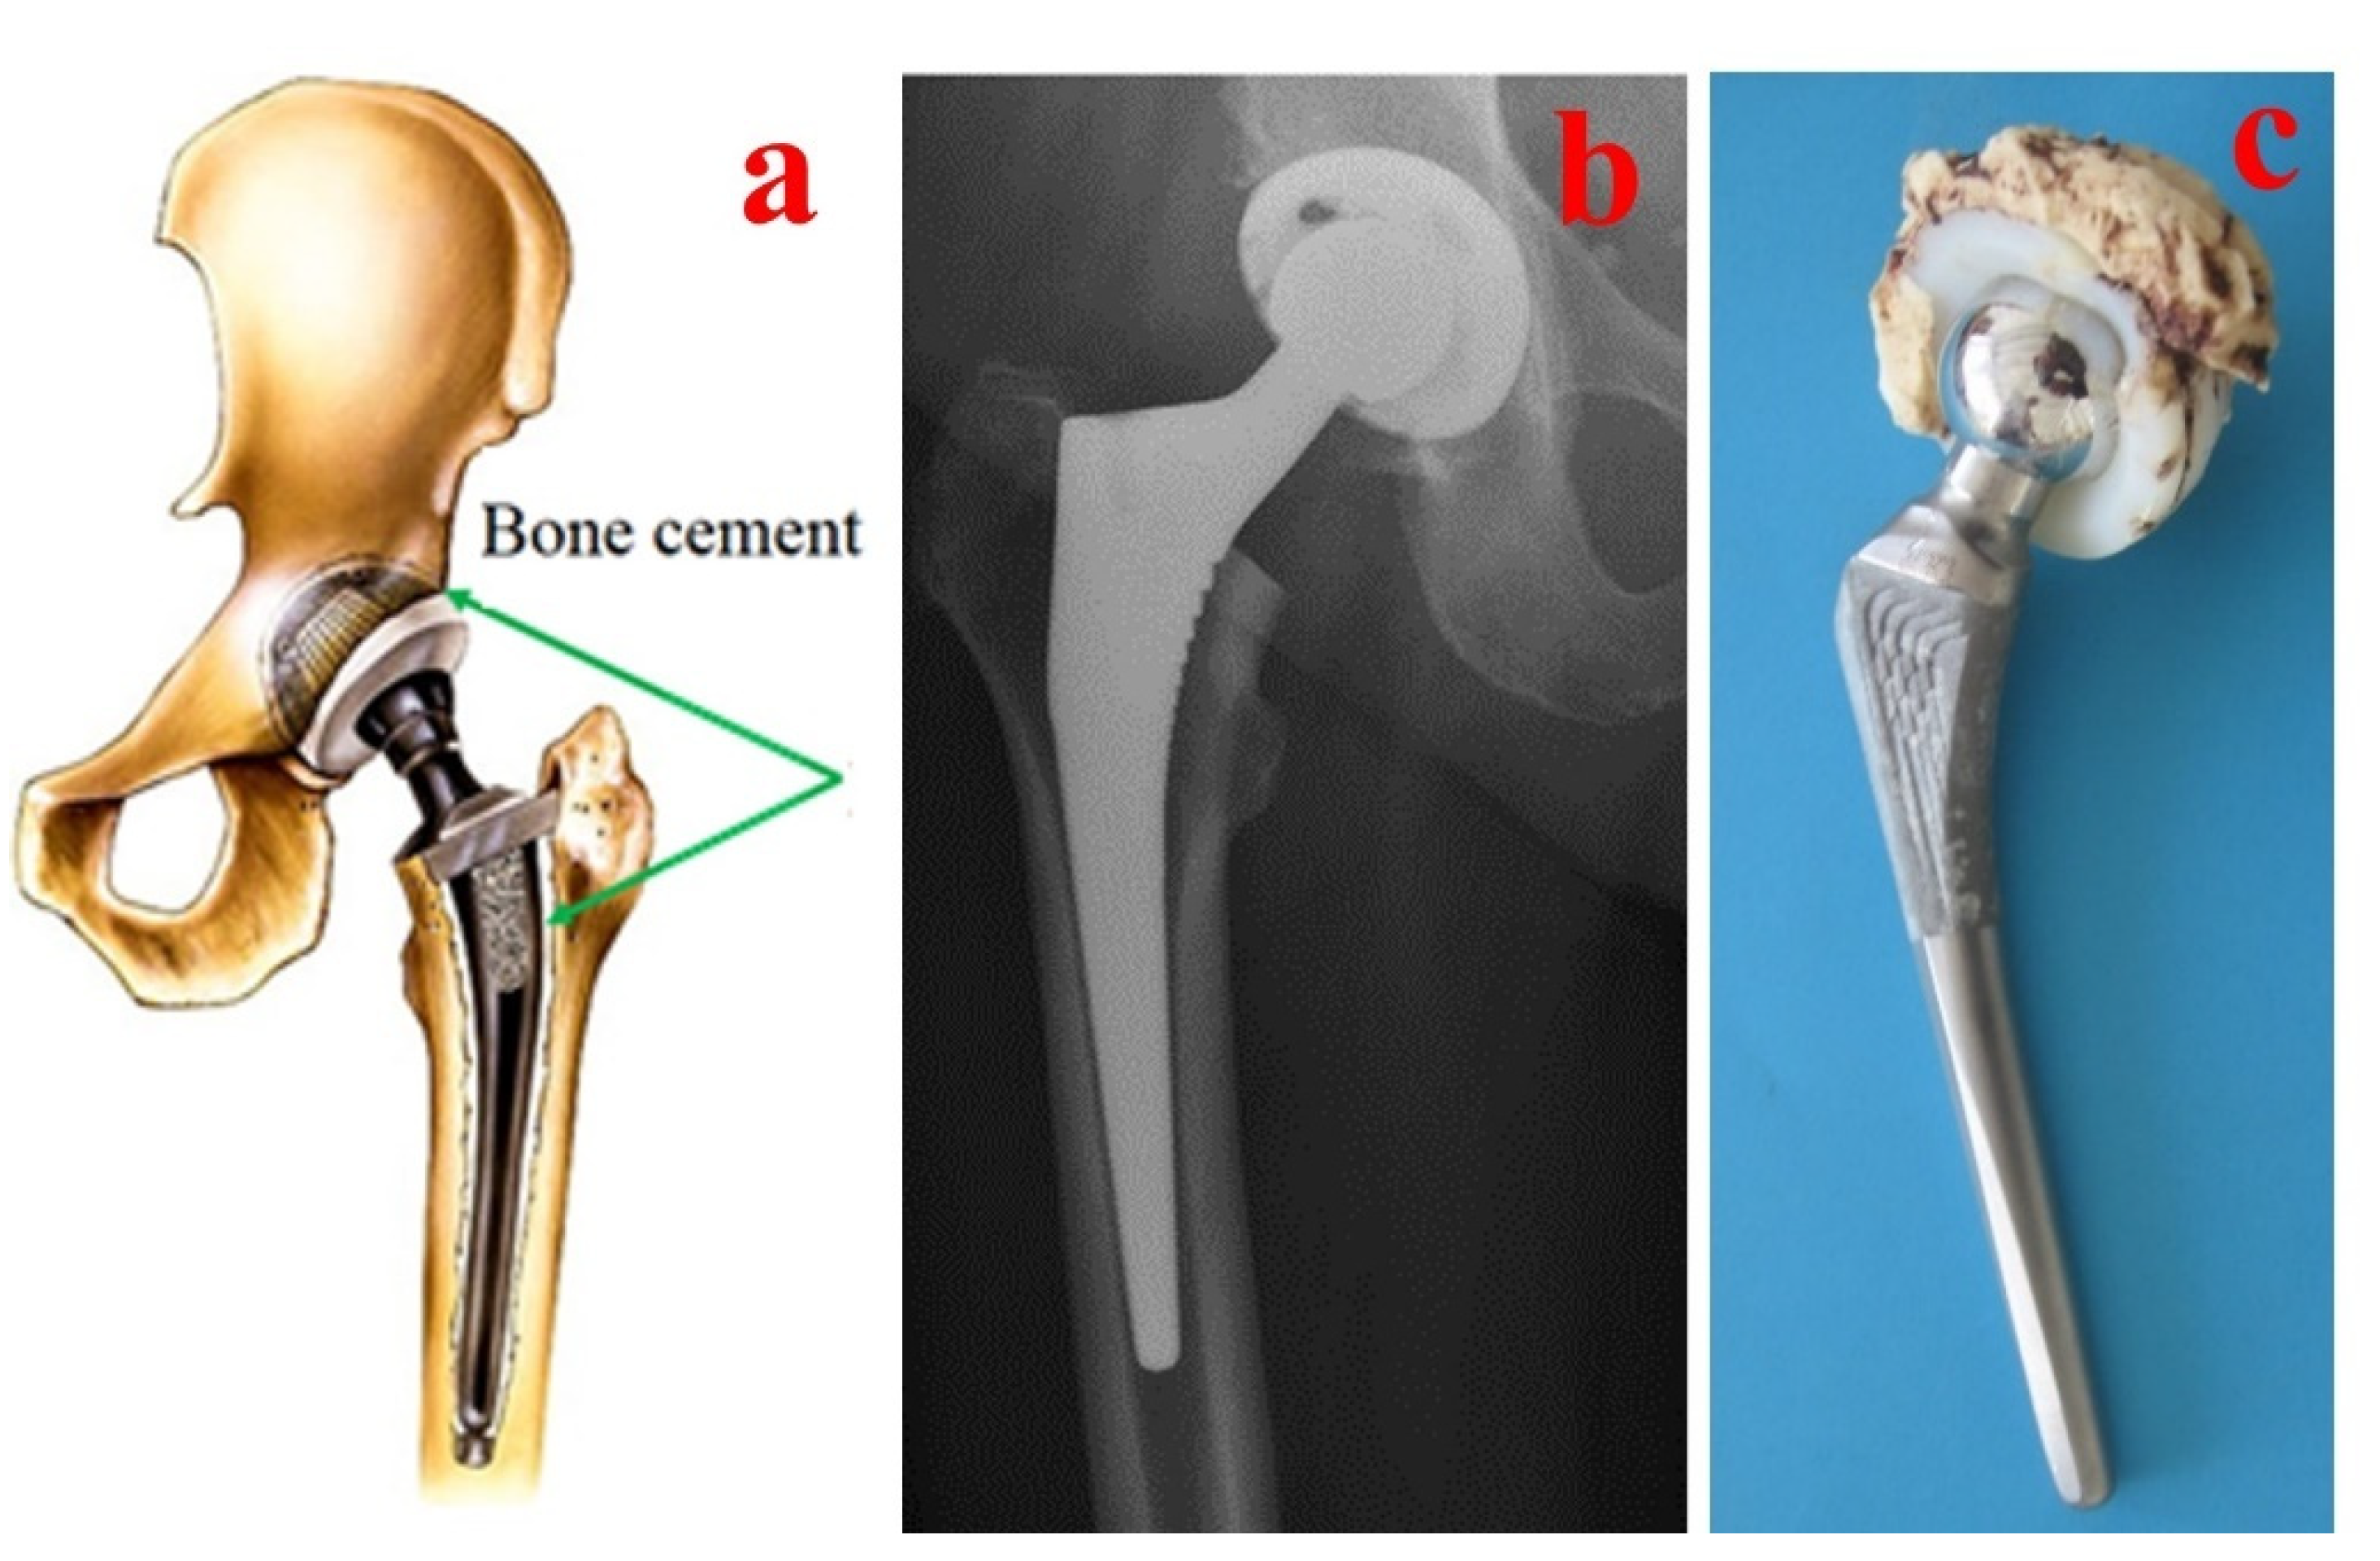

Bone cement performance is directly linked to various parameters such as the mixing method, chemicals used, viscosity, porosity, antibiotics used in the cement composition, sterilization, working temperature, physical and mechanical properties and biocompatibility [61,62]. Additionally, different procedures for intraoperative handling of the bone cements are used in clinical practice. For classical hip arthroplasty, the bone cements are pressured inside the prepared bone and prosthesis components are inserted after into the cement (Figure 3), but in some specific cases such as hip resurfacing prostheses (e.g., Birmingham Hip Resurfacing Prosthesis), the bone cements are pressured inside the femoral head before the insertion of the prosthesis component into the prepared bone (Figure 4).

Figure 4. Aspects regarding the handling of bone cements for resurfacing hip prosthesis (e.g., BHR) fixation: (a) bone preparation; (b) cement pressure into the prosthetic components; (c) postoperative radiography; (d) failed BHR hip prostheses [63].